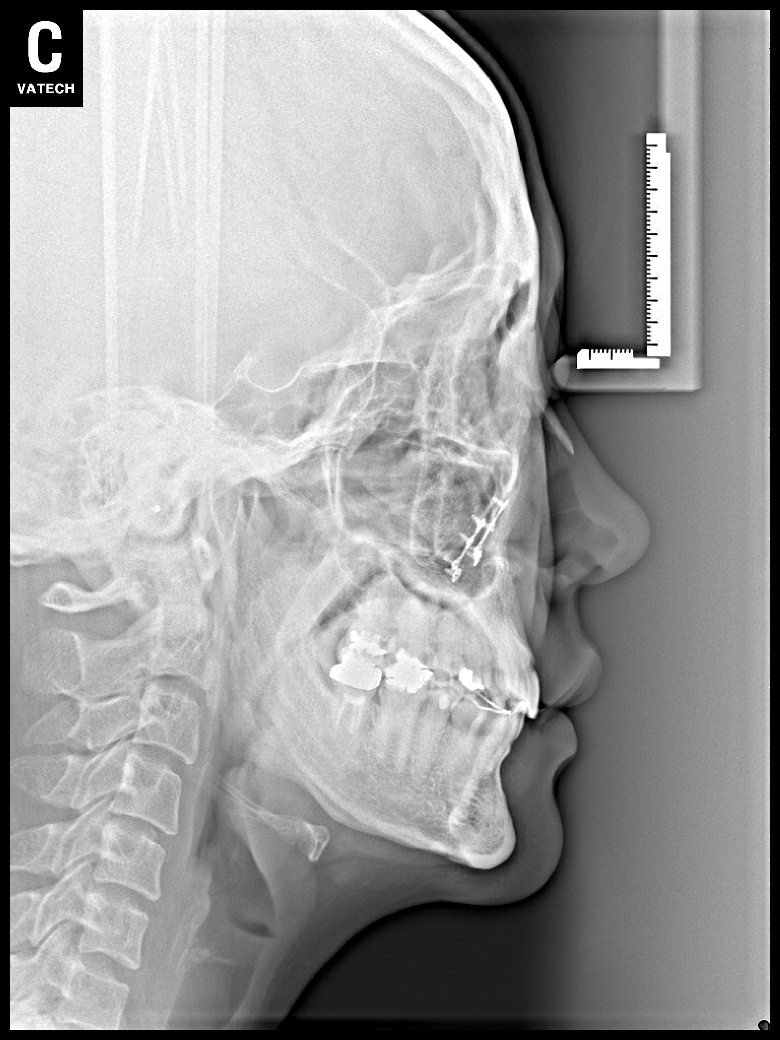

치료 후 사진입니다.